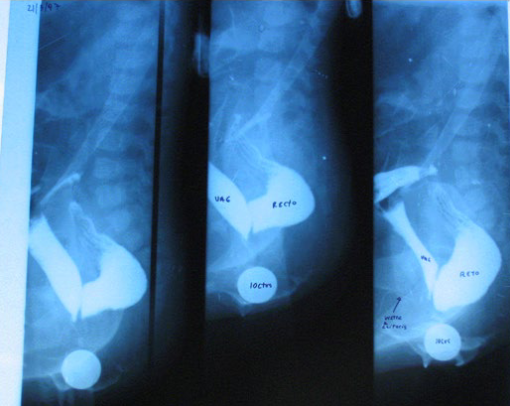

Negative Rectoanal Inhibitory Reflex in Anorectal Manometry...It is Not Always Hirschsprung's Disease

Fernandez J, Oviedo A, Messere G, Ortiz G, Breden X, Berger M and Bigliardi Román. 7(2): 01-07.